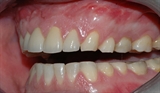

figur I

Bildet viser et eksempel på moderat tannslitasje som følge av tanngnissing.

Slitasjen er spesielt tydelig i overkjeven.